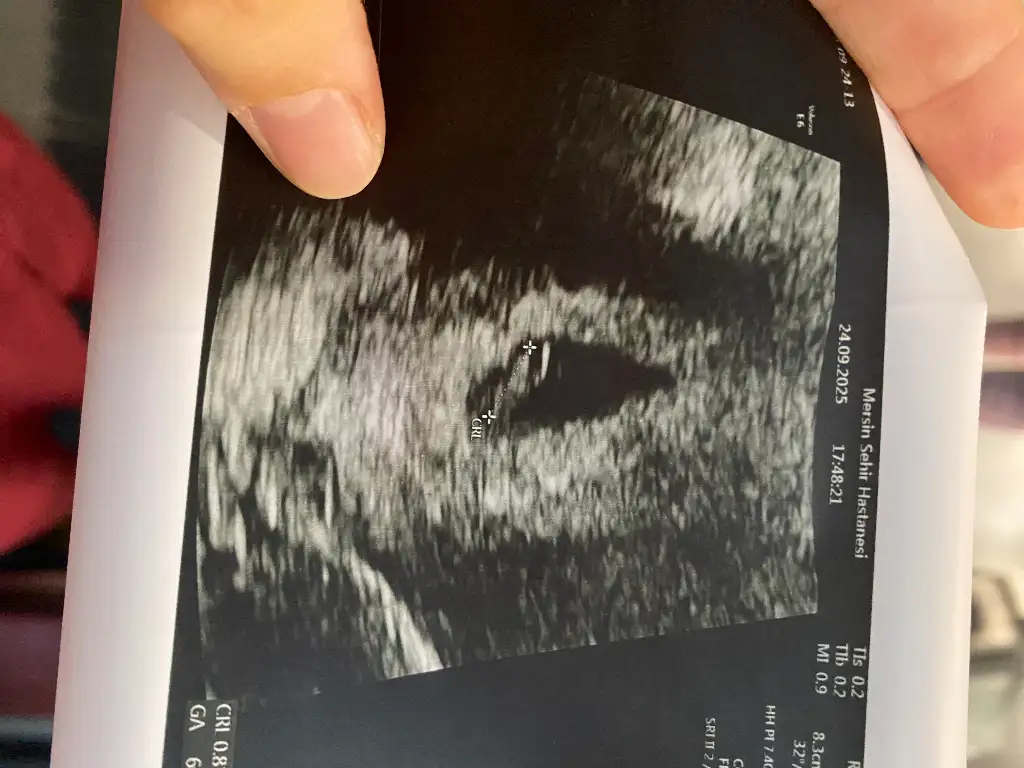

Cinsiyet tahmini yapabilen varmı?Bu grup, anne olma hayali kuran güzel kalplerin bir araya geldiği, sevgi dolu bir yerdir.

Alttan muayenede görünebilir ancakKızlar 4 haftalık kese görülür mü

Karında gördü 4 haftalık dedi ovulasyon gününden hesapladı O zamanAlttan muayenede görünebilir ancak

Vay süper 4 haftalık ben de hep zar zor alttan göründü maşaAllah karından görünmüşKarında gördü 4 haftalık dedi ovulasyon gününden hesapladı O zaman

Son adete göre 7 haftalık olmam gerekiyor ama 4 deyince ovulasyona göre mi hesapladı oVay süper 4 haftalık ben de hep zar zor alttan göründü maşaAllah karından görünmüşsağlıkla kucağınıza alın inşaAllah